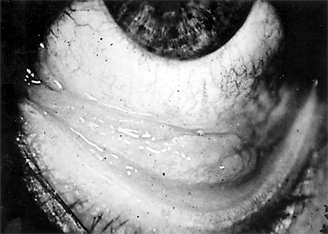

In adults, the conjunctiva of both tarsi-especially the lower tarsus-have papillae and follicles (Figure 5-3). Since pseudomembranes do not usually form in the adult, scarring does not usually occur. Superficial keratitis may be noted superiorly and, less often, a small superior micropannus (< 1-2 mm). Subepithelial opacities, usually marginal, often develop. Otitis media may occur as a result of infection of the auditory tube.

Figure 5-3: Acute follicular conjunctivitis caused by inclusion conjunctivitis in a 22-year-old man with urethritis. (Courtesy of K Tabbara.)